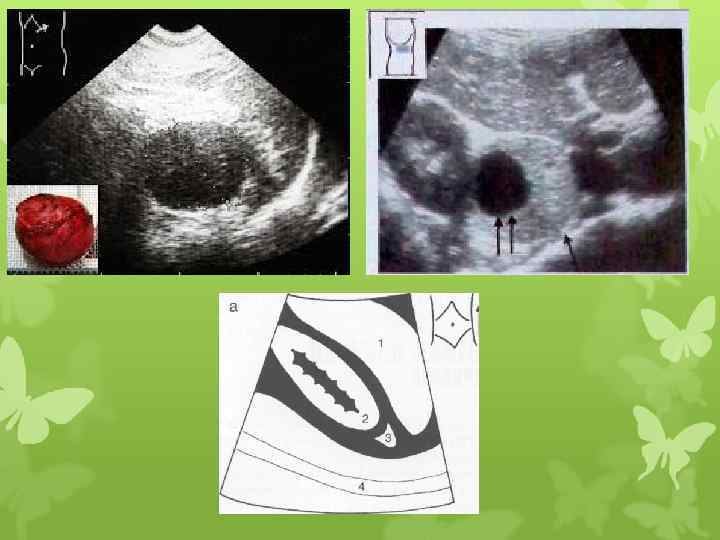

Надпочечник выделен белыми стрелками. В норме имеет треугольную форму, ровные и четкие края. Как мы видим на изображении, надпочечник охватывает своими контурами верхний полюс почки. Неизмененные надпочечники не всегда визуализируются при ультразвуковом исследовании ( ситуация меняется при наличии опухоли - надпочечники становятся видны).